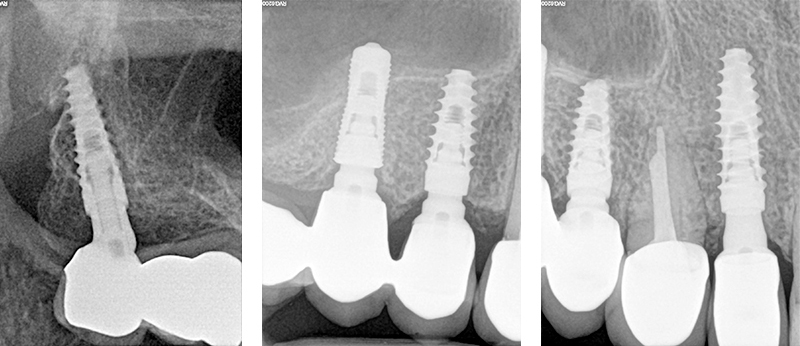

OPT con pterigoideo 17, rialzo trans-crestale 15 e Socket Shield su 12 e applicazione monconi per le conometrie protesiche parallele

Fig. 15 - OPT con pterigoideo 17, rialzo trans-crestale 15 e Socket Shield su 12 e applicazione monconi per le conometrie protesiche parallele

Fig.  16, 17, 18 - OPT con pterigoideo 17, rialzo trans-crestale 15 e Socket Shield su 12 e applicazione monconi per le conometrie protesiche parallele

Figs. 32, 33, 34 - Radiografie finali impianti 17, 15, 14 ad un anno dal carico con guarigione del rialzo di seno trans-crestale del 15, impianto pterigoideo 17 e Socket Shield 12